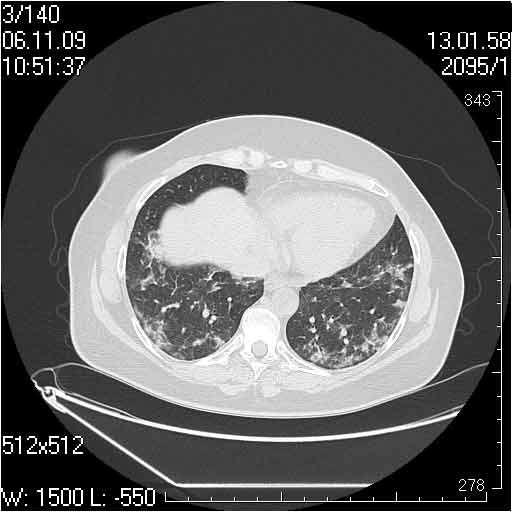

Случай №1

Женщина 50 лет.

Случай 1: изменения характерны для интерстициальной пневмонии (IIP/UIP idiopathic interstitial pneumonia/usual interstitial pneumonia); говорить о конкретной форме без открытой биопсии затруднительно.